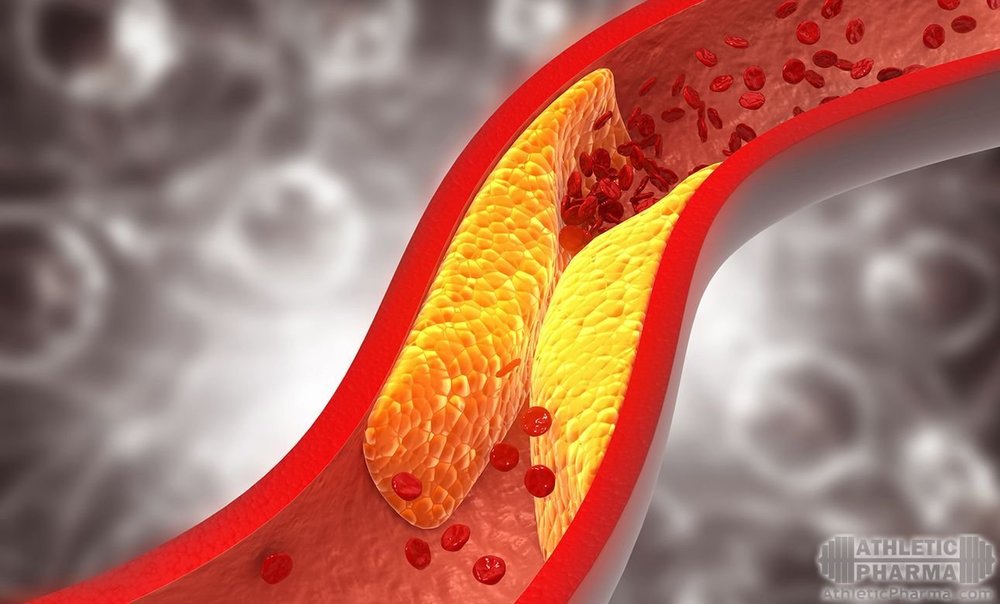

По статистике, атеросклероз является основной причиной сердечно-сосудистых заболеваний и инсультов. Кровеносные сосуды забиваются органическими и неорганическими отложениями, подобно трубам в старом доме без системы очистки. Однако наттокиназа, если предположения исследователей окажутся верными, действует как лекарственный "жидкий сантехник" (простите нас за такую дурацкую аналогию, мы не смогли удержаться).

По статистике, атеросклероз является основной причиной сердечно-сосудистых заболеваний и инсультов. Кровеносные сосуды забиваются органическими и неорганическими отложениями, подобно трубам в старом доме без системы очистки. Однако наттокиназа, если предположения исследователей окажутся верными, действует как лекарственный "жидкий сантехник" (простите нас за такую дурацкую аналогию, мы не смогли удержаться).

Сразу несколько крупных исследований на животных за последние двадцать лет показали, что дополнение рациона питания пищевой добавкой из натто сокращает утолщение сонной артерии, по сравнению с контрольной группой на плацебо. В то время как недавнее испытание на людях выступает доказательством пользы наттокиназы при подавлении формирования холестериновых бляшек у пациентов с атеросклерозом (Рин и коллеги, 2017). Важно уточнить, что улучшение клинической картины было даже более статистически значимым, чем при приеме традиционных лекарственных средств (20 мг симвастина).

Из того же испытания на людях: у субъектов, получавших наттокиназу на протяжение 26 недель, значительно снизились уровни триглицеридов, общего холестерина и "плохого" холестерина ЛПНП, – так называемой главной троки подозреваемых при развитии сердечно-сосудистых заболеваний.

К сожалению, на сегодняшний день механизмы антиатеросклеротического воздействия наттокиназы почти не изучены. Есть лишь предположение, что, скорее всего, оно обуславливается сочетанием антитромботических, антикоагулянтных и антиоксидантных свойств активного компонента.